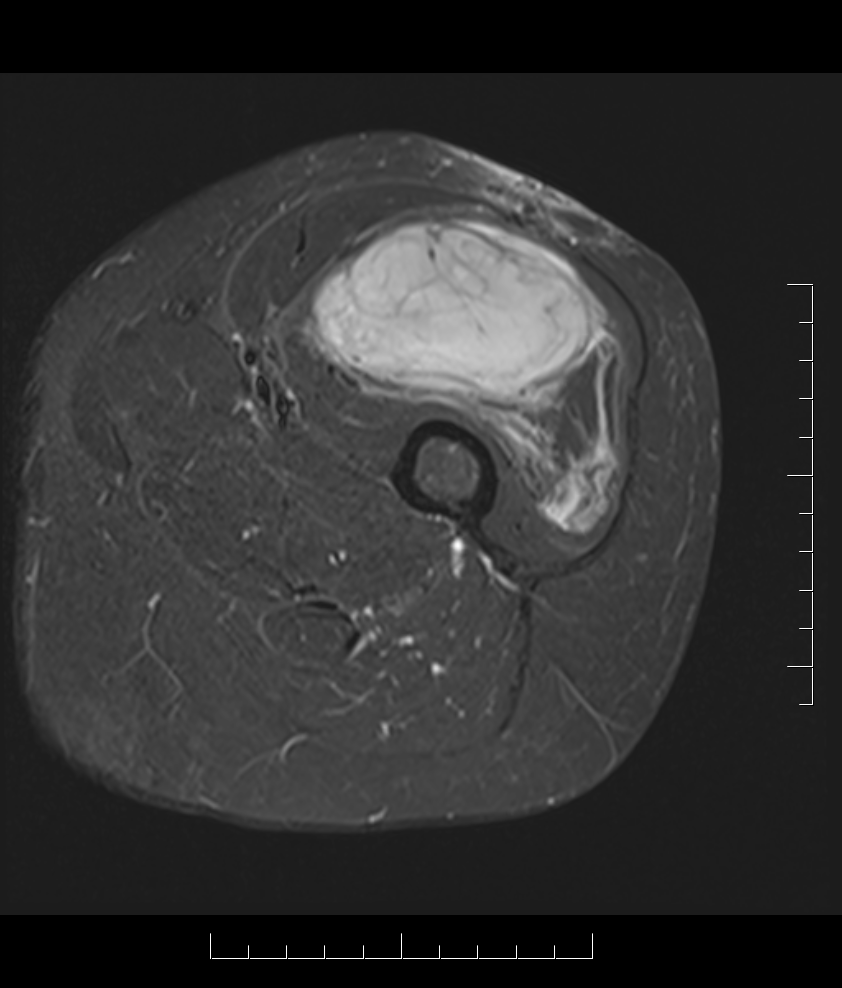

MRI

Anatomy / neurovascular involvement

Sarcoma medial thigh

Sarcoma anterior thigh

Sarcoma posterior thigh

Sarcoma buttock

Sarcoma knee

Superficial tibial sarcoma

Forearm sarcoma